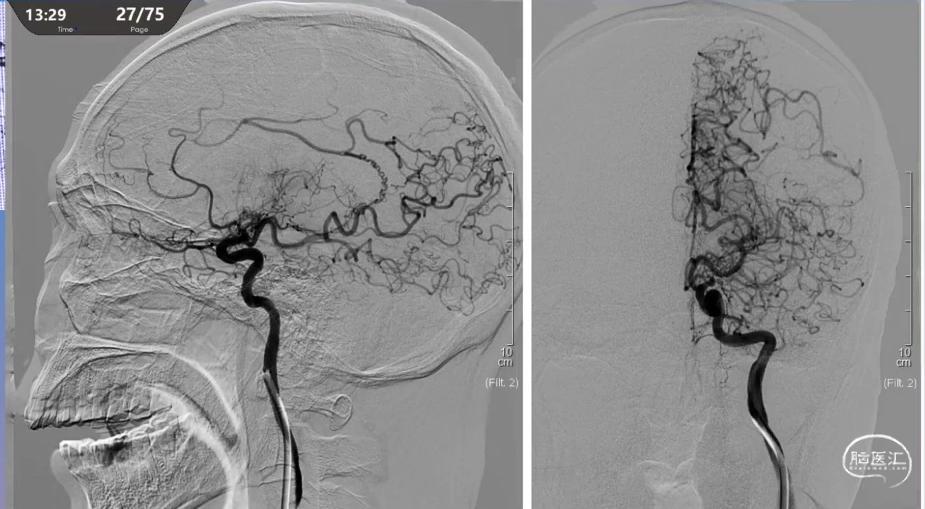

双侧椎动脉闭塞,左椎是一个优势,我们过去球囊成型扩张,支架植入。

术后得到了很好的结果。